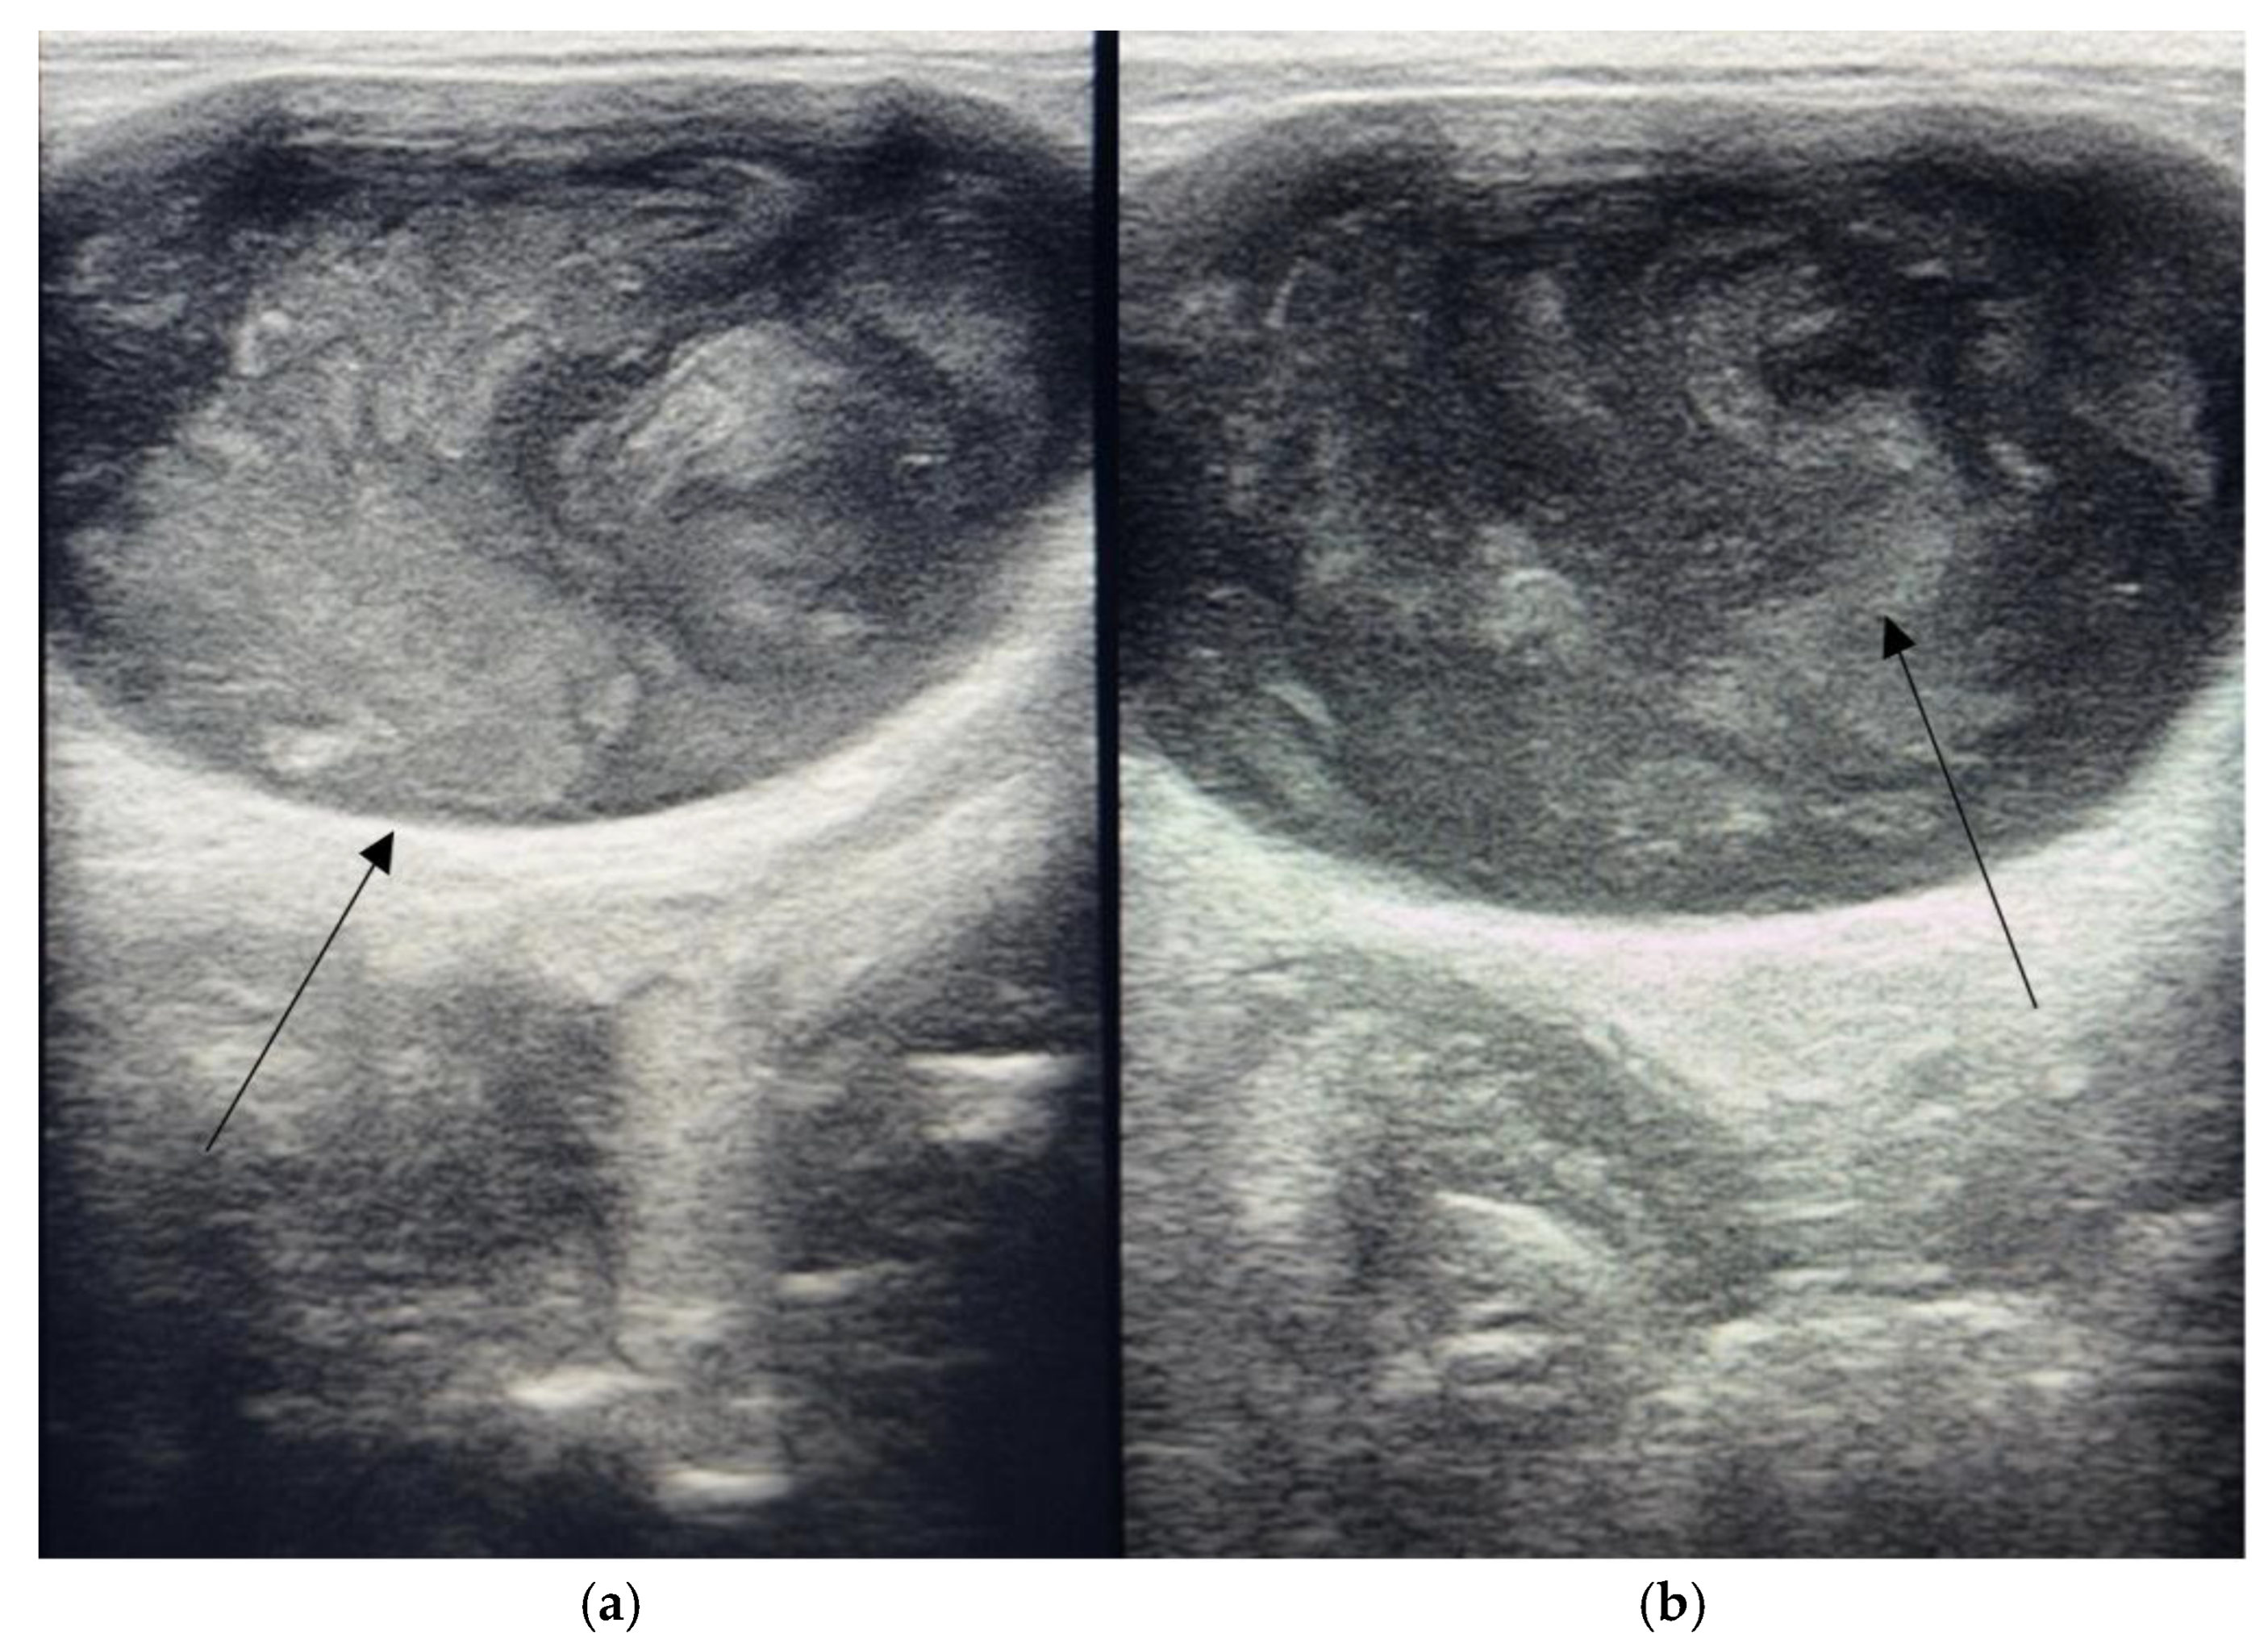

2. Case Study